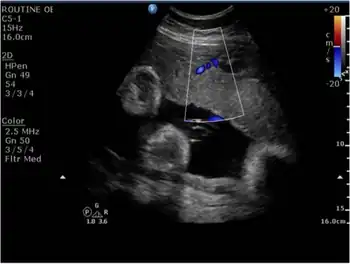

Doppler of the myometrial placental junction showing a reduced flow at the time of diagnosis of intrauterine growth restriction.

In terms of the diagnosis of Intrauterine growth restriction, the use of ultrasound is essential[25]